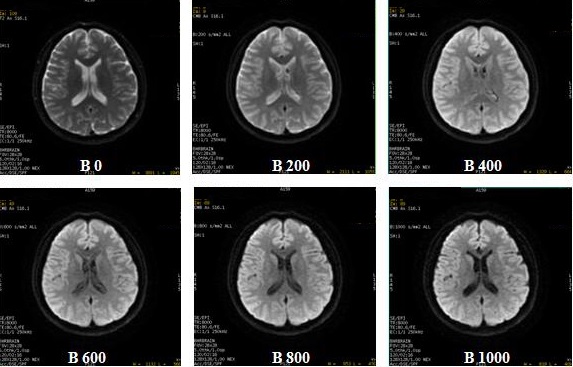

b-value

• The maximum b-value is 10,000 s/mm2. The maximum b-value may vary depending on the Diffusion Direction selected (3in1 versus TETRA, etc.). Higher b-values may eliminate T2 shine-through, improve visualization of white matter tracks, and therefore be useful in differentiating sub-acute versus chronic infarcts. The strength of the diffusion weight is determined by controlling the strength and duration of diffusion gradients via controlling a quantity called b-value. Multiple b-values can be acquired within a single scan. A CMB image is created for each b-value if it is a Diffusion All or Tetrahedral scan.

• Recommended b-values for abdomen: 500 - 700.

• Recommended b-values for brain: 1000 - 1500.

Figure 7. Varying b-values

• Multiple b-value is only available with DWI and not with DTI.

• From the Diffusion tab, specify the NEX for each b-value. As NEX increases, SNR increases.